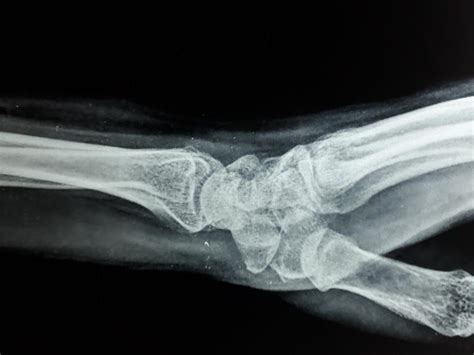

Diagnosing a Broken Scaphoid Bone

Diagnosing a broken scaphoid bone involves a combination of physical examination and imaging tests. A healthcare provider will typically:

• Order imaging tests, such as X-rays, to visualize the bone

However, X-rays may not always show a scaphoid fracture, especially in the early stages. In such cases, additional imaging tests may be required, including: